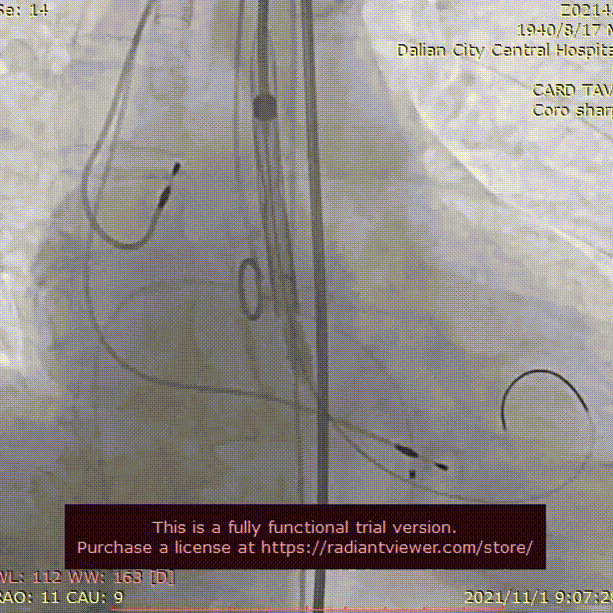

术中影像

LCA造影

RCA造影

主动脉根部造影

22mm球囊充分扩张

瓣膜初始定位, 选择0位释放

TaurusElite AV26mm瓣膜,瓣上2mm 工作位造影

瓣膜形态良好 位置理想